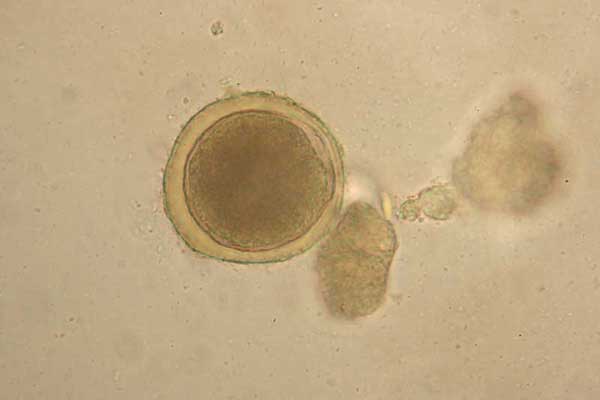

Микрофотографии яиц гельминтов Toxocara canis

Раздел: Фотоэссе